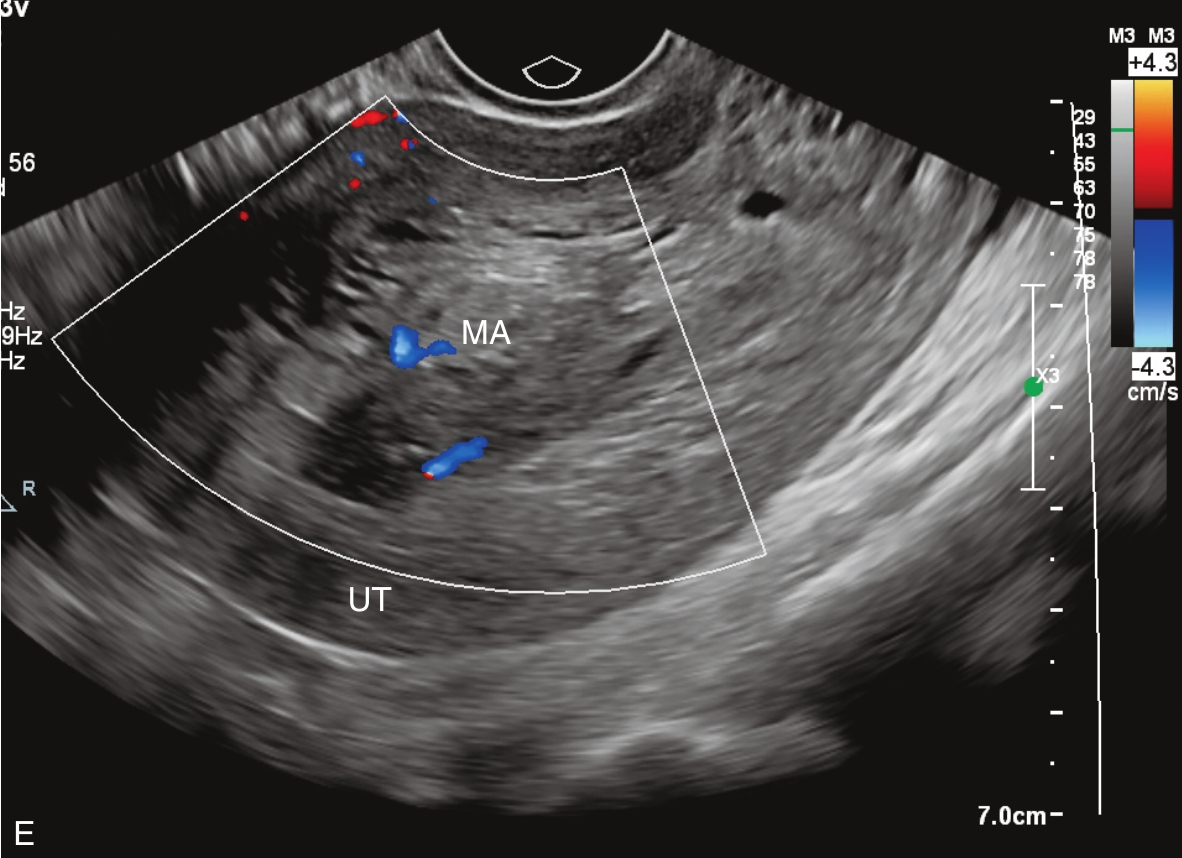

经阴道超声检查见图3-10-1。子宫前位,宫体大小5.6cm×6.9cm×6.5cm,宫腔内查见7.1cm×2.6cm×3.5cm不均质稍强回声,其内回声极不均匀,其内可见多个无回声区,最大无回声区的最大径为0.8cm,周边及其内探及丰富血流信号,该团块与子宫前壁关系密切。宫颈后唇查见囊性占位,大小为2.5cm×1.3cm×1.9cm,囊液清亮,未探及明显血流信号。双附件区未见确切占位。超声检查结果:宫腔内占位,宫颈后唇囊性占位。

图3-10-1 常规超声声像图

A.子宫矢状切面显示宫腔内稍强回声;B.子宫横断面显示宫腔内强回声;C.子宫矢状切面显示宫颈管内占位;D.宫颈管内占位的血流情况;E.宫腔占位的血流情况;F.宫颈囊性占位(箭头所示)。UT:子宫;C:宫颈;MA:肿物。